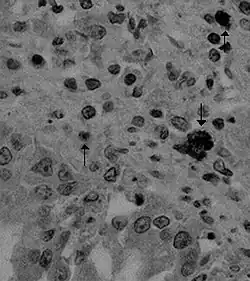

Das Virus dringt in die Zotten des Dünndarms ein und vermehrt sich dort. Darmerkrankungen können mit einer virusinduzierten Apoptose (programmierter Zelltod) von Zellen der Epithelschleimhaut des Dünndarms zusammenhängen.[9] Ursprünglich wurde angenommen, dass das Hunde-Coronavirus schwere Magen-Darm-Erkrankungen verursacht, aber heute werden die meisten Fälle als sehr mild oder ohne Symptome angesehen.[10] Eine schwerwiegendere Komplikation des Hunde-Coronavirus tritt auf, wenn der Hund auch mit dem Parvovirus infiziert ist.[11] Eine Coronavirus-Infektion der Darmzotten macht die Zellen anfälliger für eine Parvovirus-Infektion. Gelegentlich wird aber immer noch über tödliche Darmerkrankungen von Hunden berichtet, die mit dem Caninen Coronavirus ohne das Vorhandensein eines Parvovirus assoziiert sind.[12][13] Dies könnte mit der hohen Mutationsrate zusammenhängen, zu denen auch das Canine Coronavirus gehört.[3]